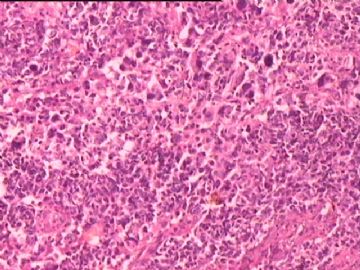

女,34y,头痛一月,右额叶占位:5*5*4cm。囊性区域,4cm。大体:3.5x3x1cm灰白间暗褐色组织一堆,质嫩。临床诊断1:胶质瘤,2:血管母细胞瘤。

同意胶质母细胞瘤。细胞异型、坏死、核分裂、血管内皮肿胀增生均可见到。

This is certainly a WHO grade IV malignant neoplasm. While most likely a glioblastoma, I would carefully rule out PNET by staining for GFAP and neuronal markers such as synaptophysin, NeuN and NSE. Rarely, PNET may shows marked pleomorphism and indistinguishable from glioblastoma on HE stain.

同意马老师的意见,该肿瘤从形态及年龄来看考虑PNET或GBM,须标记Syn、NSE、S-100、NeuN和GFAP来鉴别。